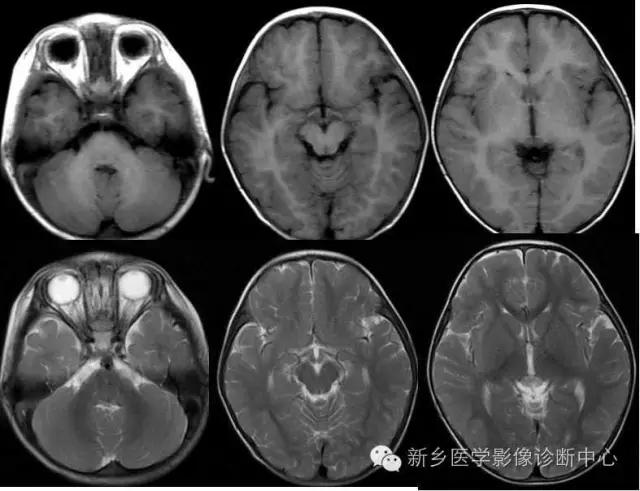

白质髓鞘形成后,与灰质在T1WI上成高信号相比较,T2WI成低信号。

在出生后6个月以内,T1WI是评估髓鞘化进展最有效的序列,与灰质相比,髓鞘化的区域在翻转恢复成像上成高信号;6个月以后绝大多数大脑白质在T1WI上成高信号,超过这段时间在评估髓鞘化过程就要依赖T2WI。到24个月时,除去位于枕顶叶侧脑室旁的终末区,髓鞘化的进程已大部分完成。这些终末区在长TR序列中呈模糊的高信号,这样的改变可以持续至30-40岁。

---I期:新生儿:出生至出生后1个月

髓鞘形成进程的MRI表现:

T1WI:高信号 T2WI:低信号

正常足月儿出生时:

放射冠中央

大脑脚、视束、桥脑、内囊后肢

丘脑腹外侧

小脑上蚓部、小脑上、下脚